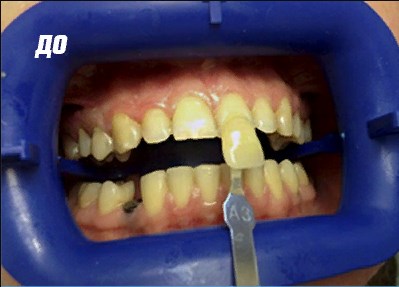

Эстетическая стоматология: фото До и После